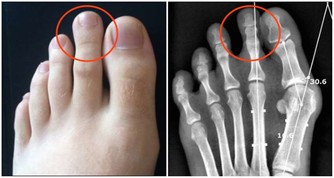

肝癌會轉移到其他部位,比如轉移到肺部、骨骼處、那麼就可能出現骨痛、胸痛的情況。